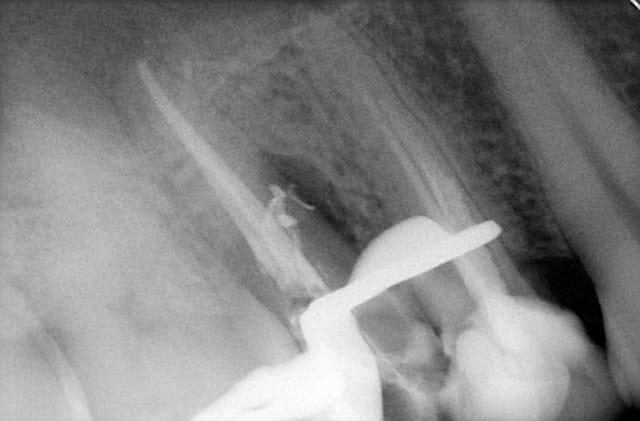

J'ai un patient qui est venu pour un "point blanc" sur la gencive dans le secteur 1. Pour moi c'est abcès qui a "fistulisé"; en prenant la radio je vois donc cette lésion dans le 1/3 moyen de la 15 et je décide de reprendre le traitement canalaire quelques jours plus tard.

Est ce que pour vous c'est un canal latéral ( comme je suis dit dès le départ en voyant cette lésion) ou bien un début de fêlure fissure de cette dent?

Salut je pense qu'il s'agit d'une fracture horizontale vu la quantité de gutta qui est partie dans la zone. J'imagine que tu as thermo compacté quand tu as obturé?

OU peut être le thermo compactage a fini d'agrandir ce qui n'était qu'une fissure au départ.

si fracture horizontale le matériau d'endo ne se serait il pas retrouvé aussi en mésial?

sur la rx il semble voir qu'il ne va qu'en distal, la fracture partielle de la racine est elle possible?

le figou

26/06/2014 à 13h59

ça dit 4-5mm localisé en mésial!!

La dent est fracturée, ça se voit très facilement, la pate a canaux est comme écrasée entre 2 blocs, (les 2 fragments). Extrais au plus vite (la fracture se verra très facilement) et implante à 8 semaines sinon l'infection va grossir et plus de paroi osseuse distale.